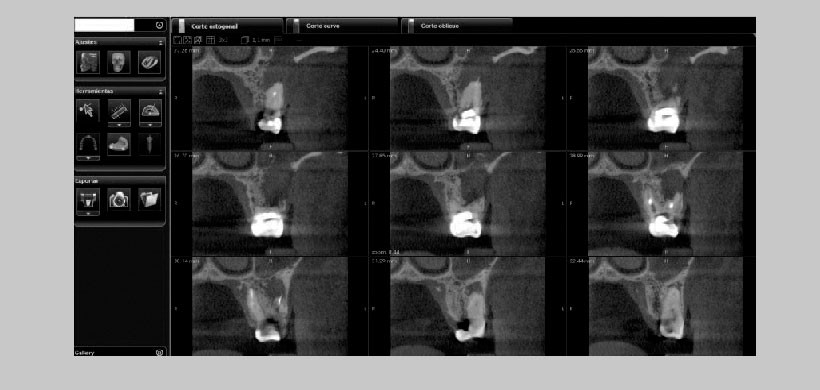

Fig 1. Estudio Cone beam revela la presencia de una comunicación buco-sinusal causada por la expansión del proceso periapical de la pieza 26. Se observa con claridad en los cortes transversales, además del velamiento por ocupación del seno maxilar izquierdo.